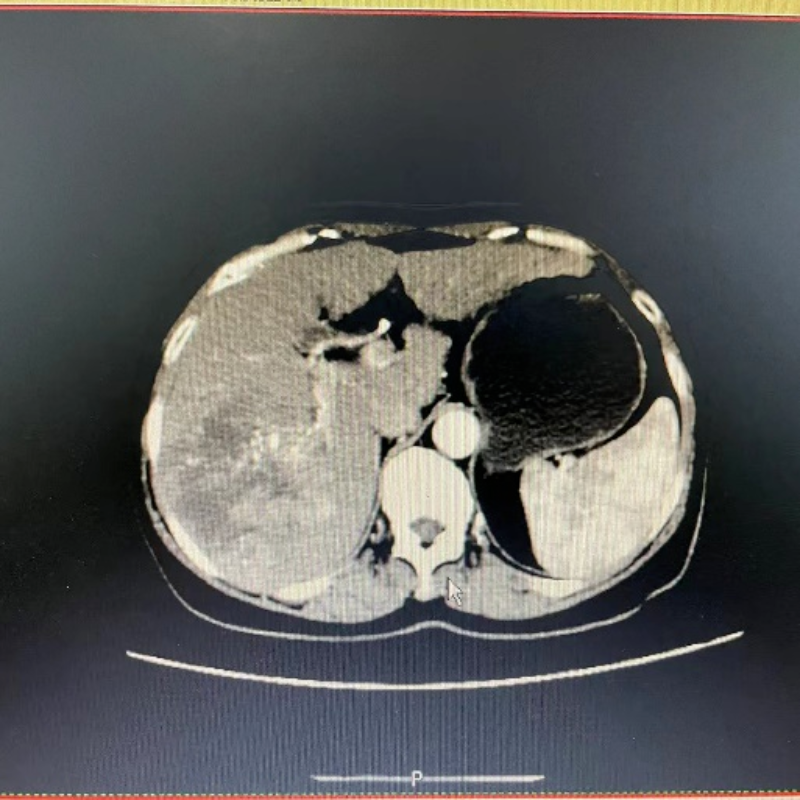

59歲的張女士(化名)因腰腹部疼痛到我院就診,在到我院就診前,她服用過止痛藥治療,但效果不佳。通過CT檢查發現其肝臟長出了直徑達11cm的腫瘤,帶著病人的期許和家屬的希望,腫瘤科醫護團隊對張女士治療方案反復討論,針對張女士的個體情況制定專項方案,決定采用微創介入行肝動脈置管術,后續返回病房行灌注化療46小時,同時聯合靶向治療及免疫治療。

介入灌注化療前。

從影像中可以看出,之前因腫瘤直徑太大而無法切除,現通過介入灌注化療+靶向治療+免疫治療后,肝內病灶已基本無活性,后續可以進行手術切除腫瘤。